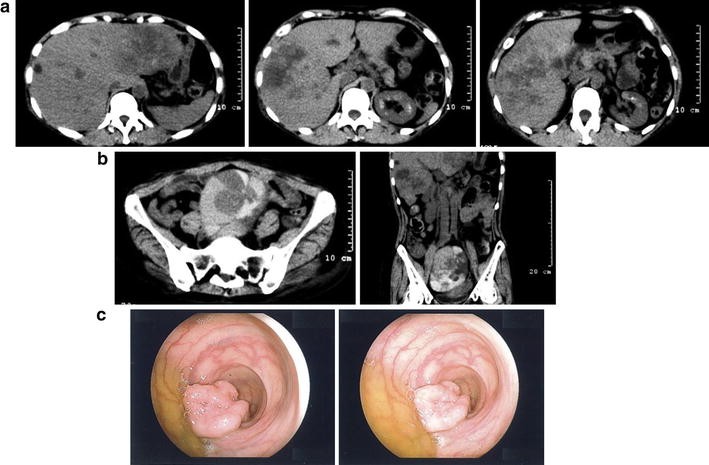

CT images and colonoscopy findings at onset. a Axial images of the liver. Multiple low-density areas suggest metastases. b Axial and coronal images of the pelvic tumor. Various densities ranging from low to high, suggesting various liquid and solid components, are seen. c Captured images during colonoscopy. A massive type 2 tumor is seen in the sigmoid colon

Colonoscopy and CT images 2 months after onset. a Captured images during colonoscopy. Compared with Fig. 1c, the tumor had grown so rapidly that the lumen was subtotally occluded. b CT images of the colon and pelvic tumors. Left panel Upper colon from the stenosis site at the sigmoid with a massive tumor is enlarged. Arrow indicates the lesion. Right panel Pelvic tumor is also extremely increased in size compared with that in the former images

Dr. Takase: The upper colon from the stenosis site at the sigmoid with massive tumor was enlarged. Compared with that in the CT images obtained at the former hospital, the ovarian tumor was also extremely enlarged (Fig. 4b).